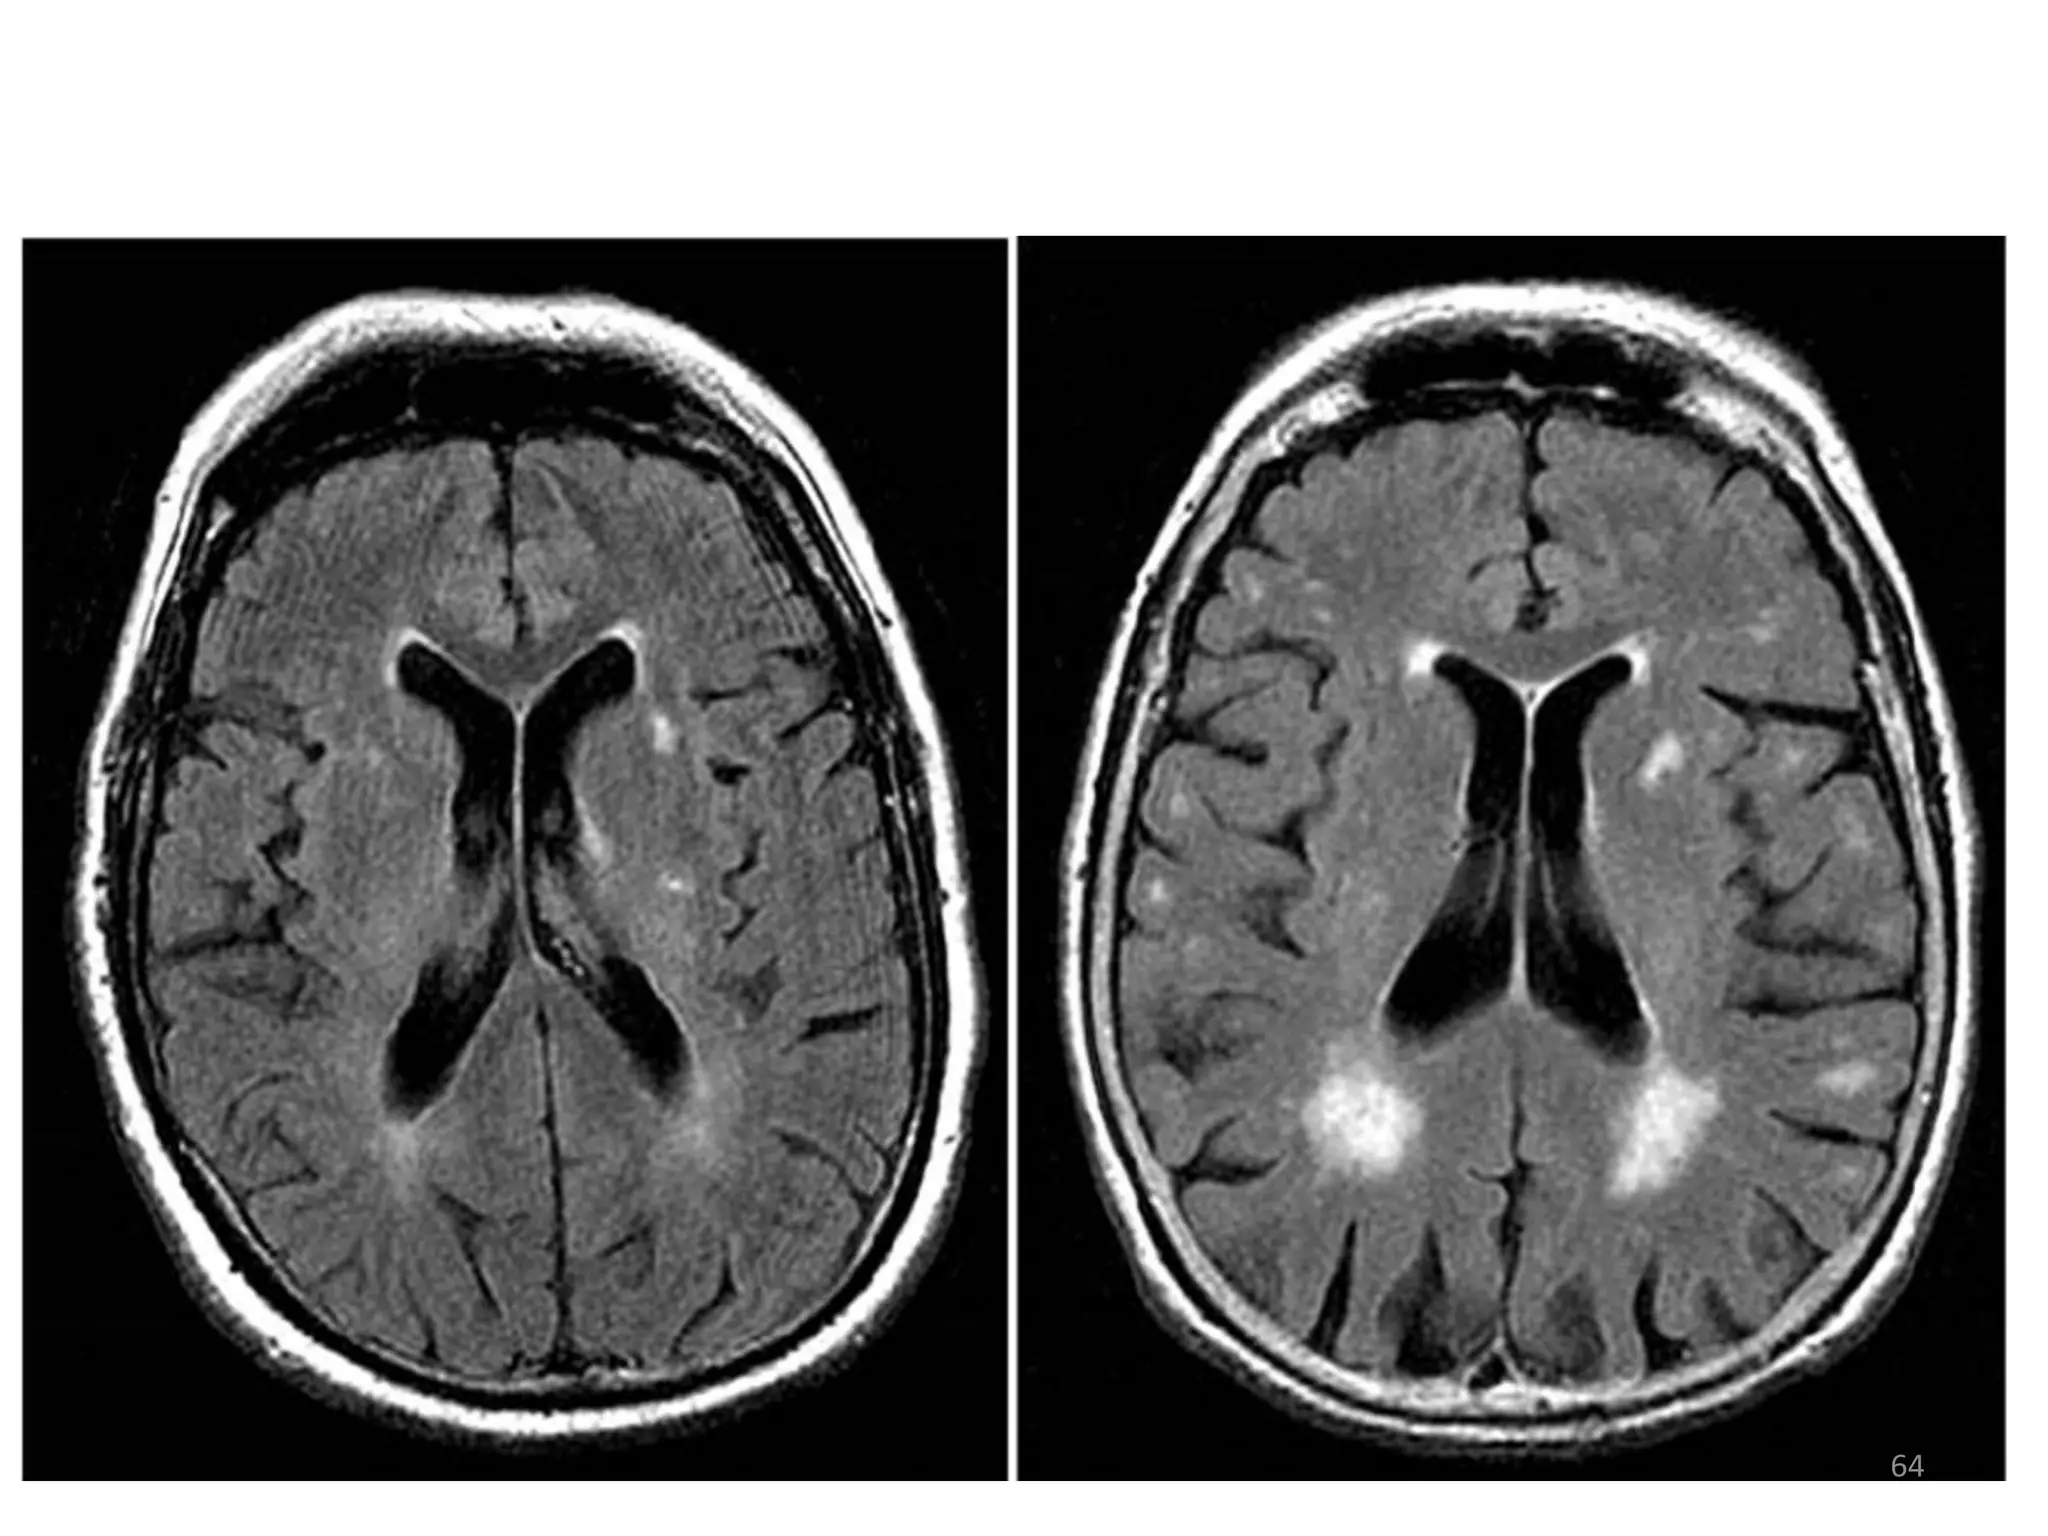

HIV-ASSOCIATED ENCEPHALOPATHY

• HIV is a neurotropic virus and infects the CNS

early during infection.

• Aseptic meningitis or encephalitis may occur

at seroconversion, and minor cognitive defects

such as mental slowness and poor memory

may develop the disease progresses.

• Dementia occurs in late disease and is

characterised by global deterioration of

cognitive function, severe psychomotor

retardation, paraparesis, ataxia, and urinary

and faecal incontinence.

• Investigations show diffuse cerebral atrophy

with widened sulci and enlarged ventricles on

imaging, and a raised protein in the CSF.

HIV-ASSOCIATED ENCEPHALOPATHY •HIV is a neurotropic virus and infects the CNS early during infection. • Aseptic meningitis or encephalitis may occur at seroconversion, and minor cognitive defects such as mental slowness and poor memory may develop the disease progresses. 62

• 63.

• Dementia occursin late disease and is characterised by global deterioration of cognitive function, severe psychomotor retardation, paraparesis, ataxia, and urinary and faecal incontinence. • Investigations show diffuse cerebral atrophy with widened sulci and enlarged ventricles on imaging, and a raised protein in the CSF. 63

• 64.